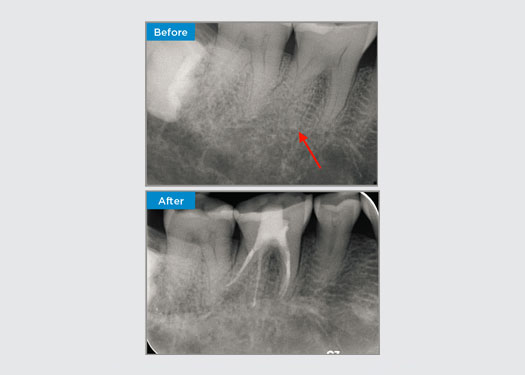

El paciente presentó periodontitis apical asintomática en la pieza dental 34. A partir de la radiografía preoperatoria, se observó que la pieza dental 34 tenía dos raíces visibles. Sin embargo, un escaneo CBCT confirmó un premolar de tres raíces y los canales se dividieron en tres en la raíz media. Una cuidadosa selección de limas es fundamental para este diente delicado.

Dr. Jack Lin, endodoncista, Sídney, NSW Australia

En esta situación, la preservación de la estructura del diente/raíz es esencial para reducir el riesgo de reborde, transporte, cierre, perforación y fractura de la raíz. La selección de casos, el diagnóstico y la planificación previa al tratamiento son importantes. La selección de limas de endodoncia con flexibilidad, eficiencia y respeto por la anatomía de la raíz natural es fundamental.